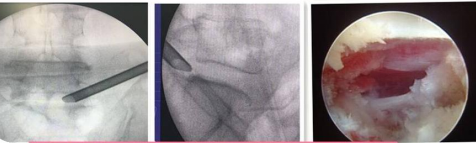

②椎間孔鏡技術(shù):科室常規(guī)熟練開展椎間孔鏡技術(shù)治療頸、胸、腰椎椎間盤突出癥、椎管狹窄癥、椎管黃韌帶骨化等。

利用椎間孔鏡從患者腰椎側(cè)方或者后方進(jìn)入達(dá)到椎間盤突出或者其他病變部位,用專用工具將突出(脫出)的椎間盤組織或病變?nèi)〕觯ㄈコ亩_(dá)到治療椎間盤突出或者椎管狹窄的目的。它的優(yōu)勢(shì)在于:局部麻醉、微創(chuàng)、切口小(僅約7mm),出血少,恢復(fù)快(第二天即可佩戴硬腰圍下地)及療效好。